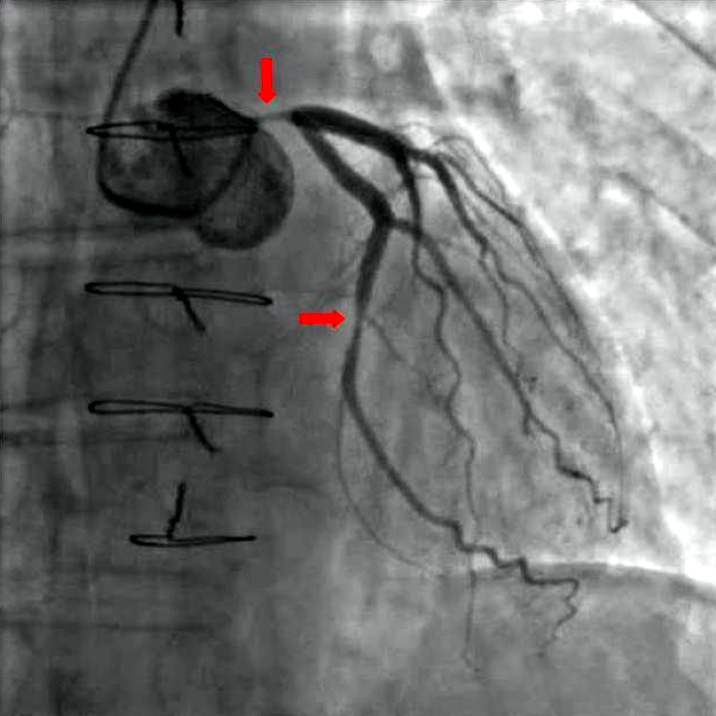

Ambulante diagnostische Herzkatheteruntersuchungen bei Herzkranzgefäßverengung, Herzklappenfehlern und nach Bypass-Operation. Koronarangiographie zur präzisen Darstellung der Herzkranzgefäße. Durchführung in der Ubbo-Emmius Klinik in Aurich mit Möglichkeit zur sofortigen PTCA und Stentimplantation.